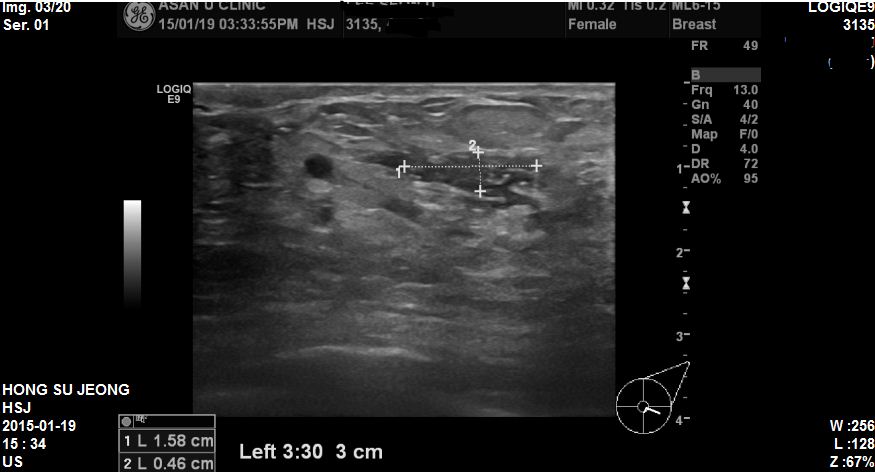

좌측유방에 만져지는 멍우리로 내원하신 62세 환자분이십니다.

본원에서 유방초음파 시행 후 좌측 3 : 00 방향에 1.5cm의혹 조직검사 시행하였고

상피내암 진단되었습니다. 만져지는 혹은 6개월전부터 만져졌었는데 만져졌다말았다해서